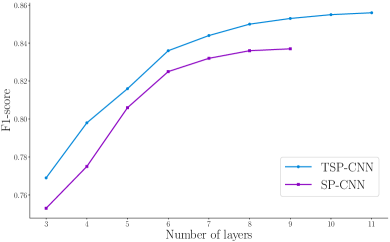

In order to come up with the number of layers which suffices for accurate nuclei detection, we train the network with layers to . The impact of number of layers is investigated in Fig. 10 for both SP-CNN and TSP-CNN. Fig. 10 reveals that for TSP-CNN and layers for SP-CNN facilitate the best computation-performance balance, i.e. more layers can mildly help but also increase computational burden. Other competing deep networks also employ 6-10 layers [5, 18].

TSP-CNN produces better results than SP-CNN even using shallower CNNs because the learned shapes adapt to the dataset. Note from Fig. 10 that a 6 layer TSP-CNN has the same level of performance as the 9 layer SP-CNN. Finally, while Fig. 10 is plotted for the UW Dataset, we found similar trends for the PSU dataset.